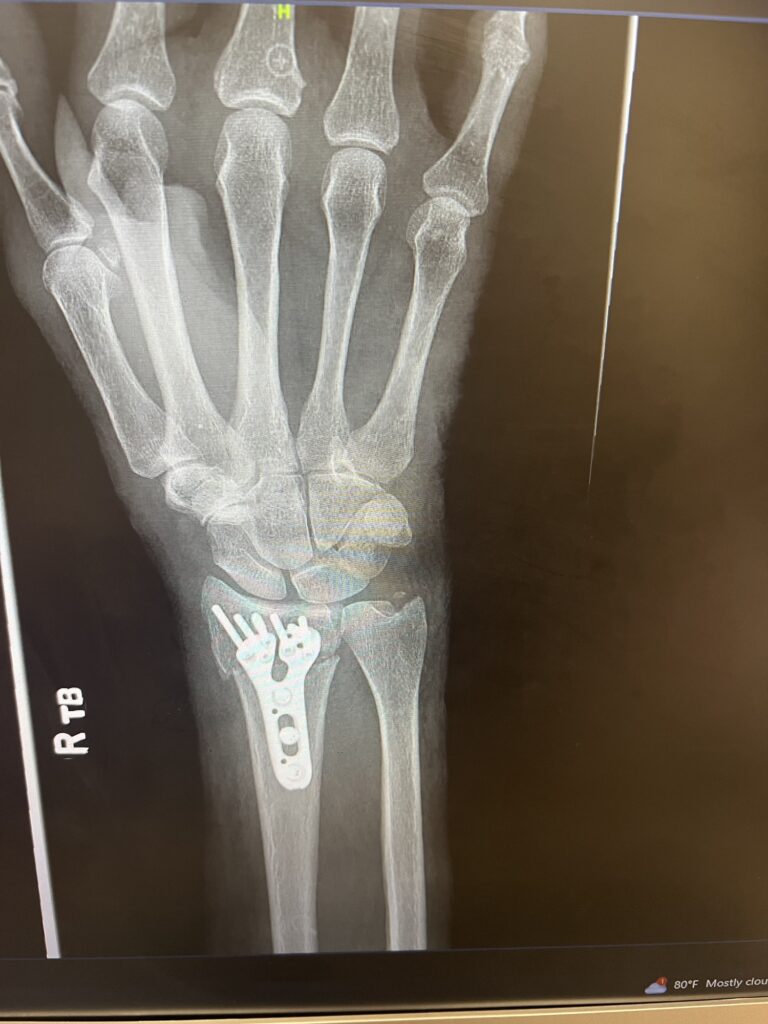

Maybe you noticed I have a splint on my arm. I was hiking in the White Tank Mountains just a week before we had planned to leave Arizona when I fell. The first thing I said was, “I broke my arm. How can I go on my mission?” This wasn’t the first challenge we’d encountered as we prepared for our mission so we just kept moving forward with faith knowing it would all work out. We had many friends and family praying for us as we left Arizona as scheduled, but as life goes there were more challenges as we learned that the broken bone had ‘displaced’ and surgery was needed. The tender mercies were there in that the doctor, I had just met in Salt Lake City, was able to do the surgery the very next day. The doctor arranged his schedule so that the stitches could be removed before flying out to Sweden. We made it to the MTC as scheduled with an additional titanium plate and 6+ screws in place.